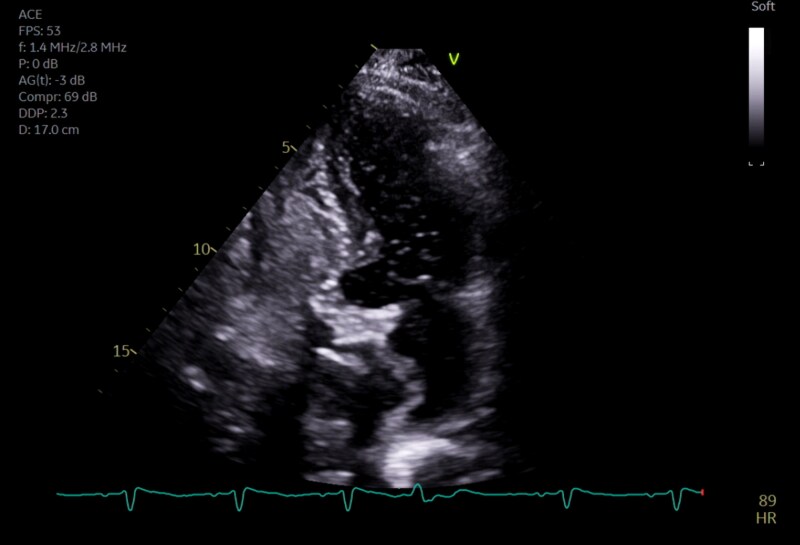

Case summary: A 77-year-old patient with severe aortic stenosis was referred for TAVI at our institution. On transthoracic echocardiography, dilatation of the ascending aorta (40 mm) and a mobile atrial septal aneurysm (ASA) were noted. Transcatheter aortic valve implantation was complicated by annular rupture and aortic intramural haematoma (IMH), managed conservatively. Three weeks after discharge, the patient re-presented with cholecystitis and underwent cholecystectomy. Post-operatively, marked hypoxaemia was noted during orthostasis. Transthoracic echocardiography showed the ASA bulging into the left atrium, with a strongly positive saline contrast study while upright. A PFO was identified on transoesophageal echocardiography and successfully percutaneously closed, with hypoxaemia resolving.